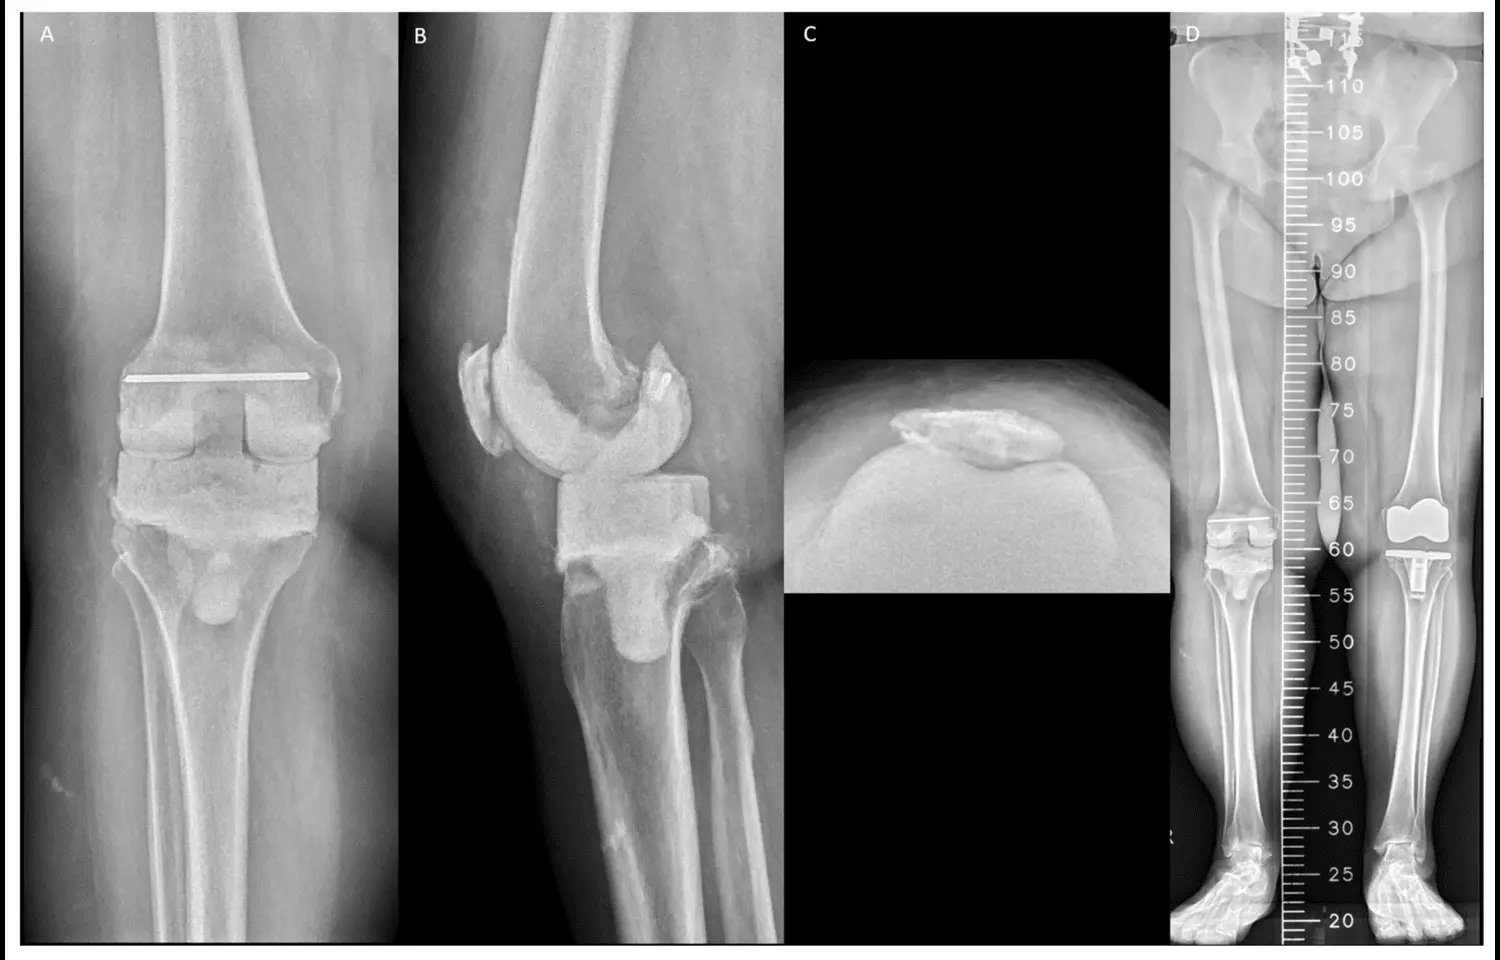

A large register-based study published in BMJ Open has reported that patients with type 2 diabetes undergoing hip or knee replacement surgery face a higher risk of long-term mortality but not an increased risk of reoperation. The research analyzed outcomes from more than 190,000 procedures recorded in Swedish national registers, making it one of the most comprehensive evaluations of diabetes and joint replacement to date.

According to the study, type 2 diabetes was linked to a greater likelihood of death after both hip and knee replacement, while the risk of requiring additional surgery remained unchanged compared to patients without diabetes. Short-term adverse events, such as complications occurring soon after surgery, were only minimally affected.